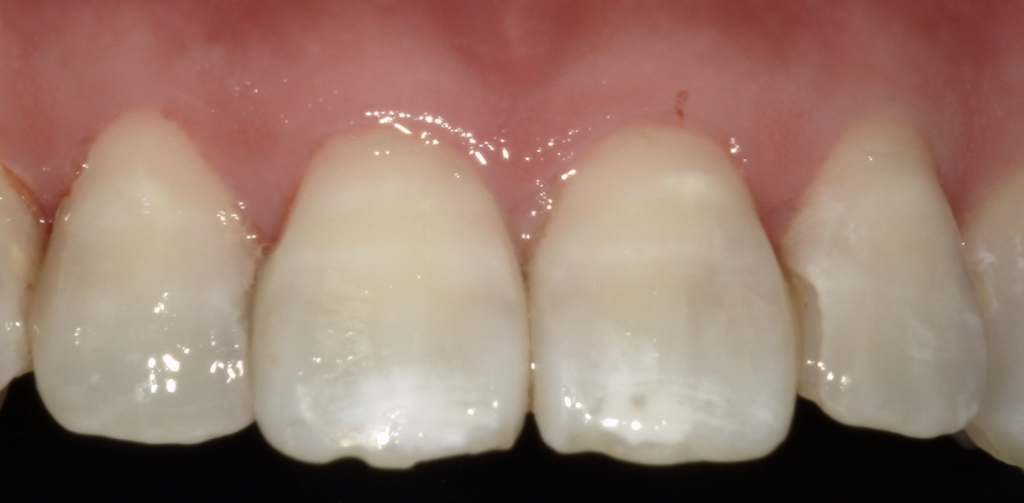

最後に、当院での治療例です♪

🔽After

処置前に比べると、処置後白い線が薄くなっていることがわかります。

このように見た目で気になるホワイトスポットも、

脱灰深さが浅ければ歯を削らずに治せるかもしれません。